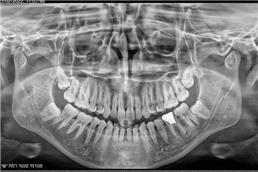

זקוקים לצילומי שיניים וחשוב לכם לקבל מענה מקצועי, אמין, מהיר ויעיל? מכון פנורמי סנטר לשירותכם! כמכון רנטגן מוביל בתחומו, אנו מבצעים צילומי שיניים ולסתות לרבות צילומי CT ואמונים על מתן שירות מקצועי, אדיב, אישי ויעיל לכל לקוח ולקוח. לנוחיותכם, אנו מספקים את מיטב שירותינו באמצעות שלושה סניפים לרבות סניף ברמת ישי, סניף ביוקנעם וסניף במגדל העמק ונשמח לעמוד גם לשירותכם לשביעות רצונכם המלאה!